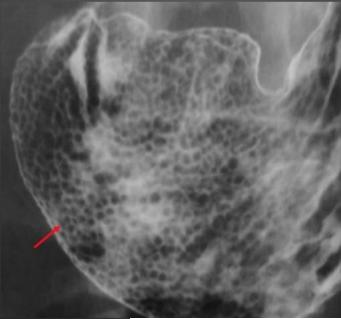

Image

chronique |

Gastrite chronique a Helicobacter pylori |